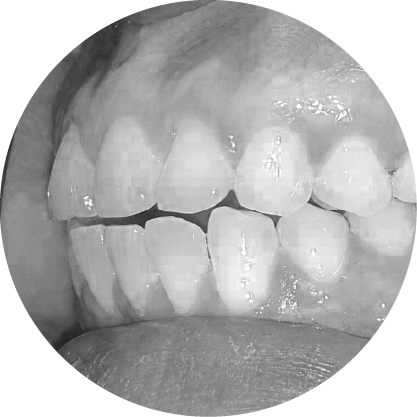

ตัวอย่างในชีวิตจริง

ฟันล่างยื่น (รีเวอร์ส โอเวอร์เจ็ต)

การแก้ไขฟันสบล่าง เพื่อความมั่นใจและการใช้งานที่มีประสิทธิภาพ

ฟันสบล่างคือภาวะที่ฟันล่างยื่นออกมามากกว่าฟันบน ซึ่งมักส่งผลต่อการเคี้ยวอาหารและความสมดุลของใบหน้า การจัดฟันสามารถช่วยปรับแนวขากรรไกรให้ถูกต้อง ช่วยเพิ่มทั้งประสิทธิภาพในการใช้งานและความสวยงามของใบหน้า